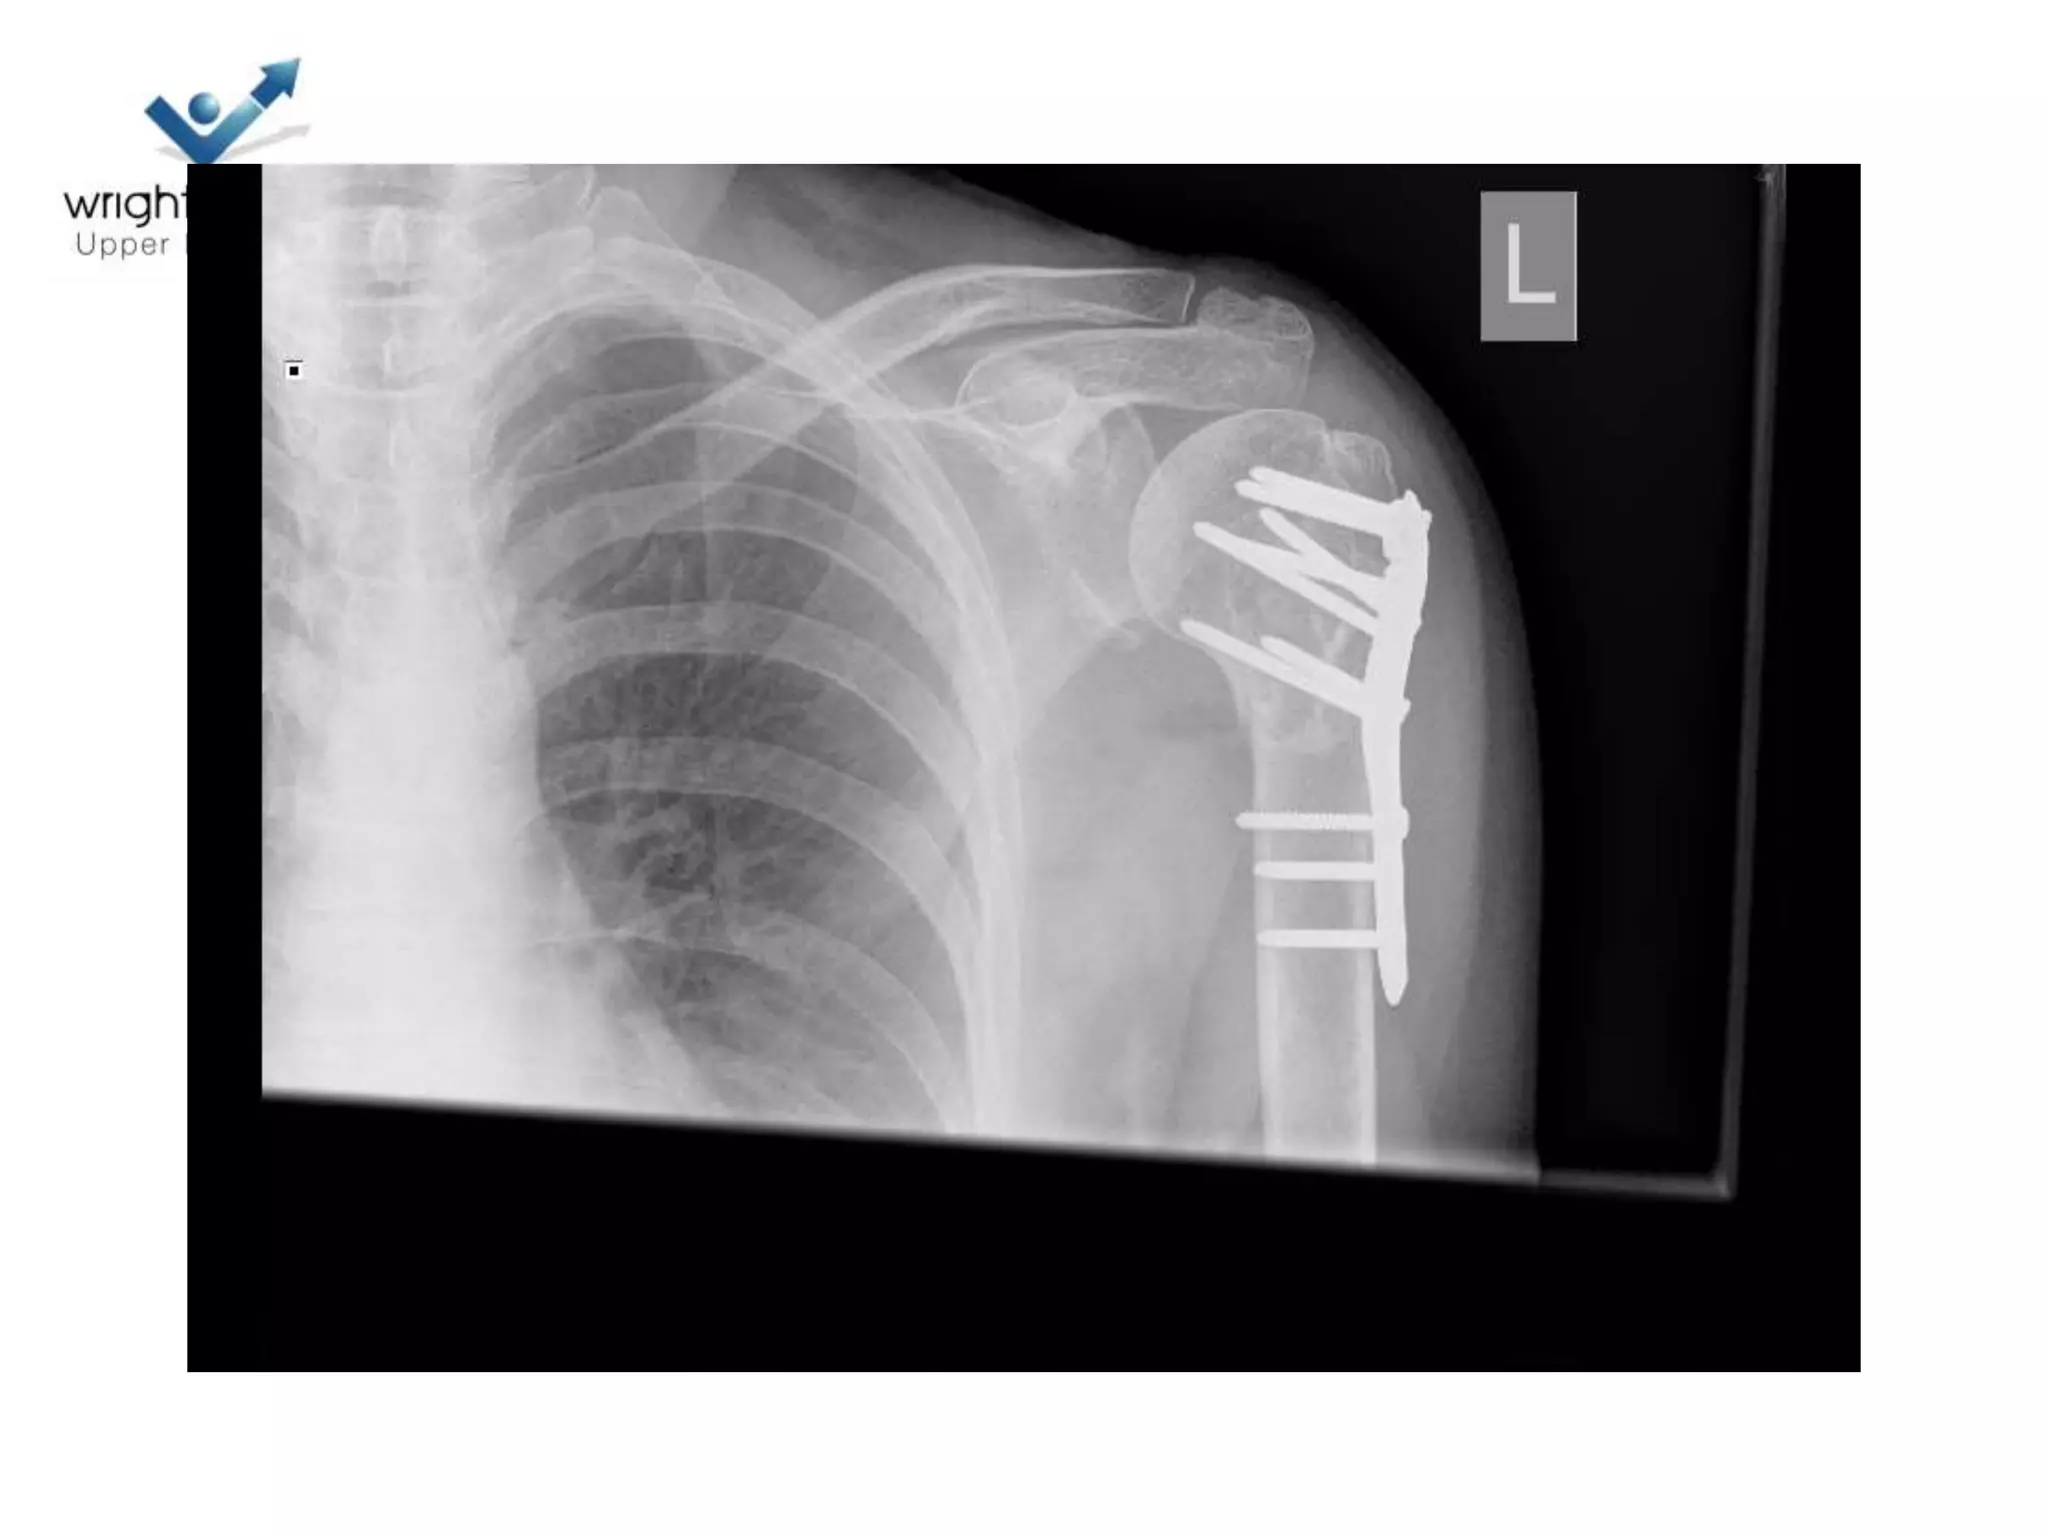

Locking plate; Tips

Locking plates: Tips

Locking plate: Tips

• Belts and braces

4 Next…

5 Next